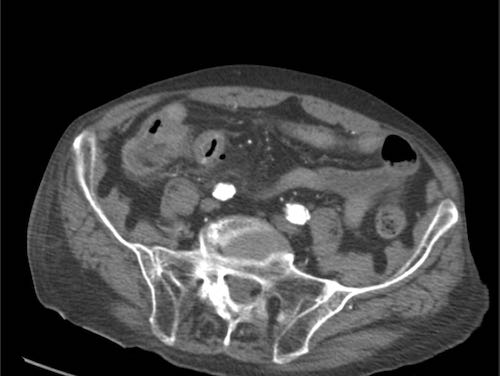

Bệnh nhân nam 85 tuổi này nhập viện với đau khu trú dữ dội, viêm phúc mạc khu trú và CRP 200, lâm sàng nghi ngờ viêm ruột thừa.

Siêu âm cho thấy một vùng nhỏ khu trú gồm mỡ tăng âm bị viêm (đầu mũi tên), chứa một ít dịch (*) và một phản âm khó lý giải (mũi tên trắng).

Chẩn đoán siêu âm dự kiến là viêm phần phụ mạc nối với vùng xuất huyết trung tâm nhỏ.

CT xác nhận thâm nhiễm mỡ khu trú và phát hiện thêm một bóng khí cũng như dày thành nhẹ của một quai ruột non lân cận.

Áp dụng từ gợi nhớ PSI-ABCD, tất cả các nguyên nhân đều được loại trừ, ngoại trừ dị vật sắc nhọn.

Sau khi tìm kiếm có chủ đích, một xương cá được phát hiện tại manh tràng (mũi tên xanh lá trên CT).

Rõ ràng, xương cá này đã gây ra thủng, và sau đó được đẩy đi bởi nội dung ruột non. Bệnh nhân được điều trị bằng kháng sinh đơn thuần và hồi phục hoàn toàn.